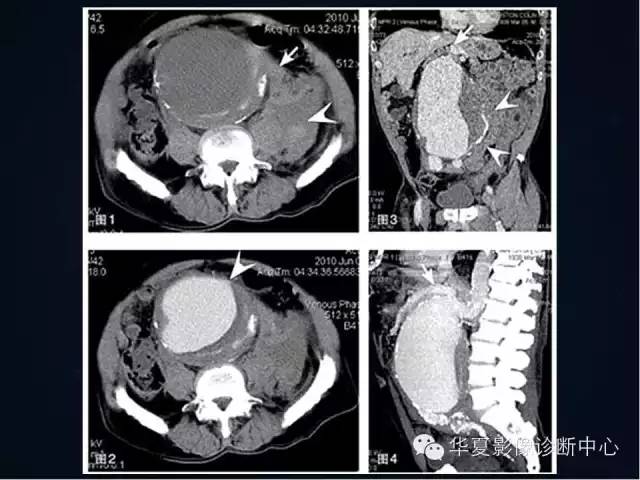

【PPT】主动脉瘤的鉴别诊断